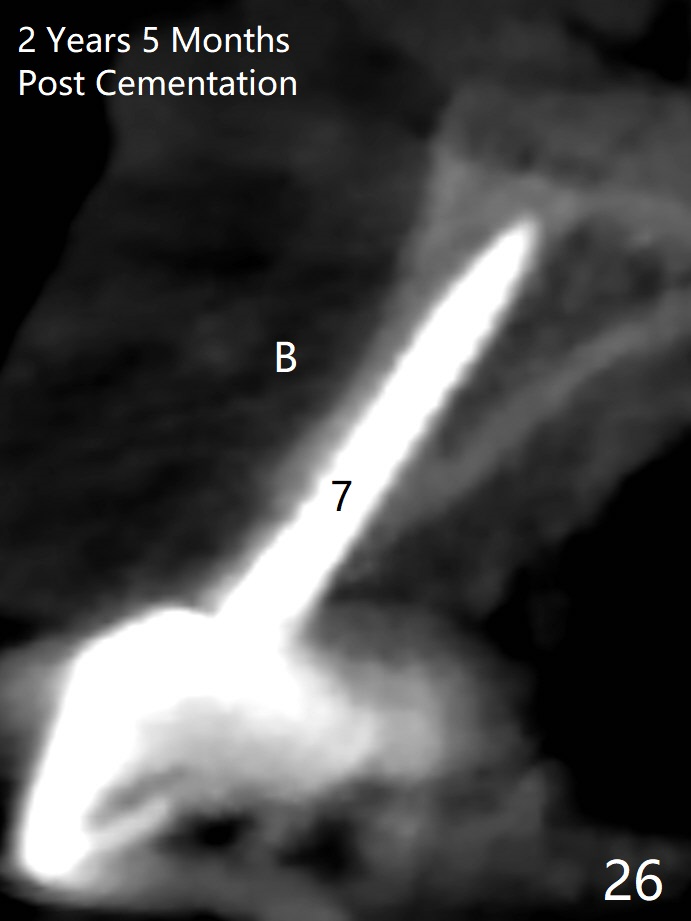

Since the ridge at #7 is ~ 4 mm, a 2.5x14 mm 1-piece implant is placed (Fig.8) after 1.2 mm (Fig.7), and 1.5 mm drills at 12 mm and 2 mm drill at 8 mm.  Later the implant is placed deeper (Fig.10).  There is no bone loss 7 or 12 months postop, respectively (Fig.11,12).  After Diode gingivectomy, there is papillary formation (Fig.13).  No provisional is provided after impression (with the abutment torqued at #6) for oral hygiene.  With access holes at #6 and 7, crowns are bonded with minimal residual cement (Fig.14 <, which is removed later).  There is no hard (Fig.15,16) or soft (Fig.17 *) atrophy 26 months postop, i.e., 13 months post cementation, due to the presence of socket shield (Fig.15 <, as compared to Fig.1).  In fact the tooth #8 has mobility and fremitus (short root/poor crown/root ratio, Fig.16); occlusal adjustment is done 13 months post cementation.  The crown is dislodged 2 years 1 month post cementation; a prefabricated post is being tried in (Fig.18).  There is no atrophy, bone loss or infection at #6 (with socket sheath (*)) or 7 two years 5 months post cementation (Fig.20-27).